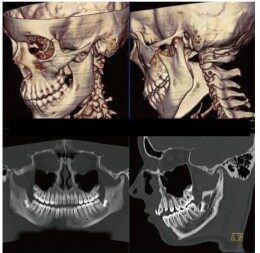

CT検査とはレントゲン(X線)を利用し身体の写真を撮影する検査です。

マルチスライスCT撮影装置

当院では、ドイツ・シーメンス社製マルチスライスCTを導入いたしました。

この装置は高速で回転し、短い時間で検査が可能な最先端マルチスライスCTで、従来の装置と比較して息を止める時間が短縮されます。また細かい情報を得ることができ、脳や腹部の血管や骨などの3D画像(立体再構成画像)を高精細に描出可能です。さらに、X線の被ばくも従来のCT装置に比べ低減されています。

頭だけではなく、全身のCTを撮ることが出来ます。